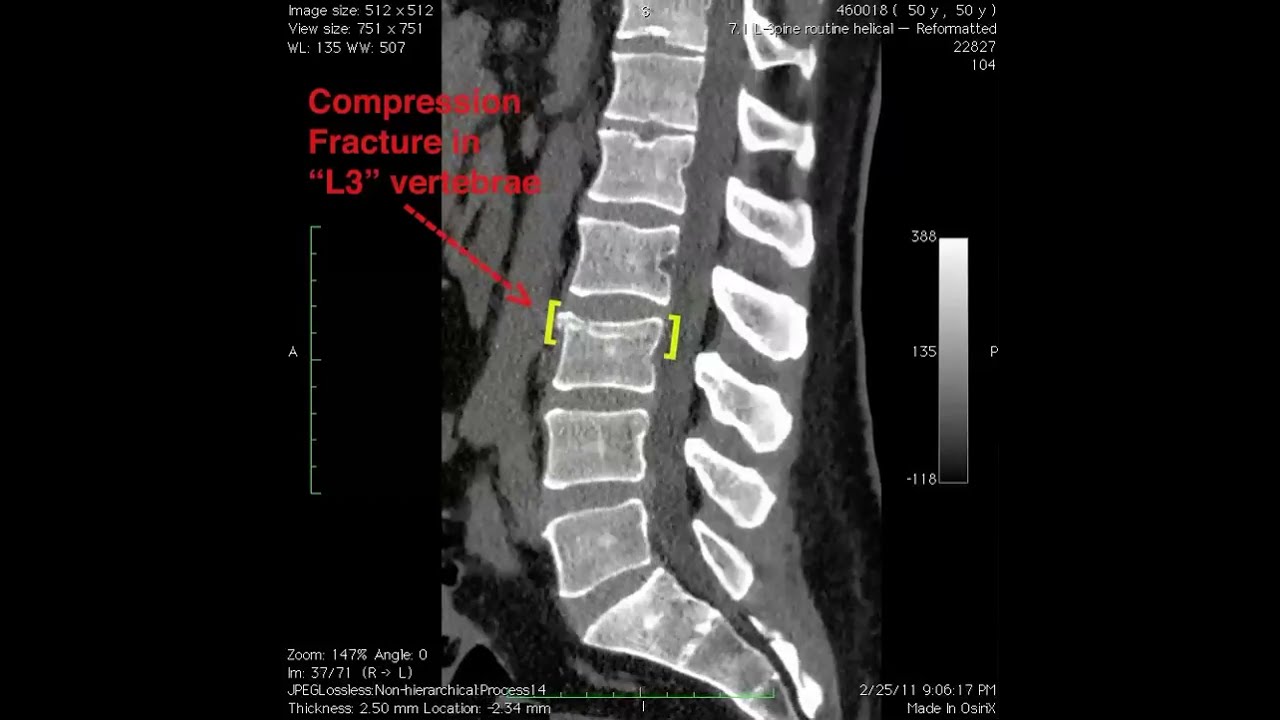

Imaging plays a crucial role in confirming the diagnosis of vertebral compression fractures and assessing their severity. What can different imaging modalities reveal?

- X-rays: Show vertebral height loss and wedge-shaped deformities

- CT scans: Provide detailed information about bone structure and fracture patterns

- MRI: Useful for detecting acute fractures and assessing soft tissue involvement

These imaging studies not only confirm the presence of VCFs but also help guide treatment decisions based on the fracture’s stability and potential for progression.